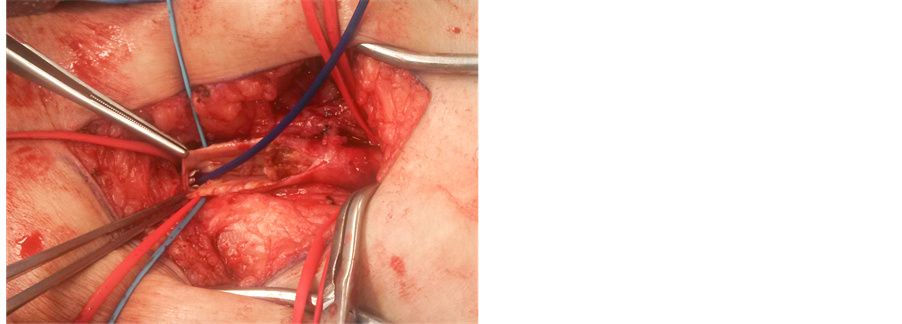

Isolation of the common femoral, superficial femoral, and profunda arteries was first carried out. A guidewire was placed distally and kept there throughout the procedure (Figure 1). Remote endarterectomy was then carried out using a Vollmar Ring Dissector [LeMaitre Vascular] (Figure 2). A Viabahn stent (GORE VIABAHN

Figure 2. Vollmar ring dissector for distal remote endarterectomy.